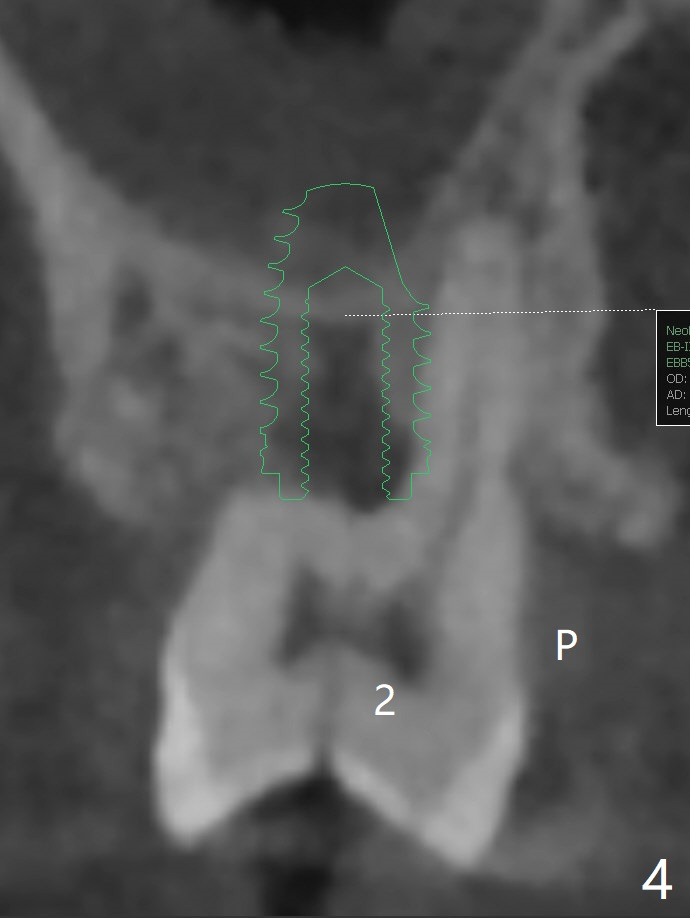

After implant placement at #13 six months post bone graft (Fig.1), reexami-nation shows that the tooth #2 cracks (Fig.2-4). The bony defect area is easier to identify with CT (between MB and P roots of #2) than without CT (M) for #13. There is no bone height reduction after extraction of #15 (Fig.5). Due to new coronal virus outbreak, the patient wants extraction first. The sinus floor perforates (*) apical to MB (Fig.6) and DB (Fig.7) roots. After debridement, sinus lift will be conducted using allograft hydrated with GEM21S liquid portion. The same mix will be used for socket preservation. With high concentration of growth factor, it is hoped that bone density in the sockets will increase quick and high enough for future implant, as compared to #13 of the same patient.